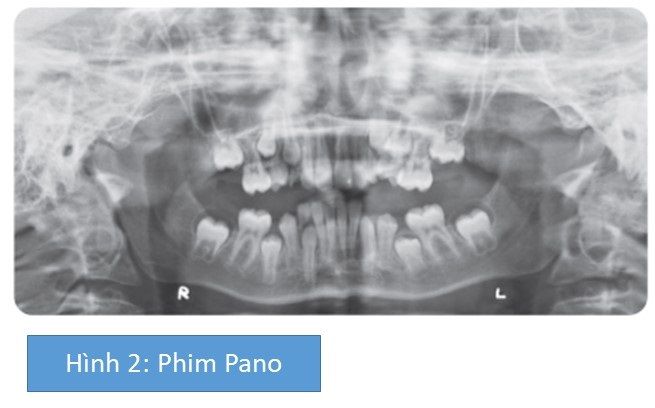

Các răng hàm nhỏ thứ 2 mọc ngầm có thể liên quan tới việc mất sớm các răng hàm sữa thứ 2 dẫn tới kết quả là di gần (và xoay trong cung hàm trên) của các răng hàm lớn vĩnh viễn thứ nhất, dẫn đến mất khoảng. Những răng hàm sữa thứ 2 nhiều khả năng mất do sâu răng; các răng hàm lớn vĩnh viễn thứ nhất có những hố rãnh đã trám bít và chưa được phục hồi.